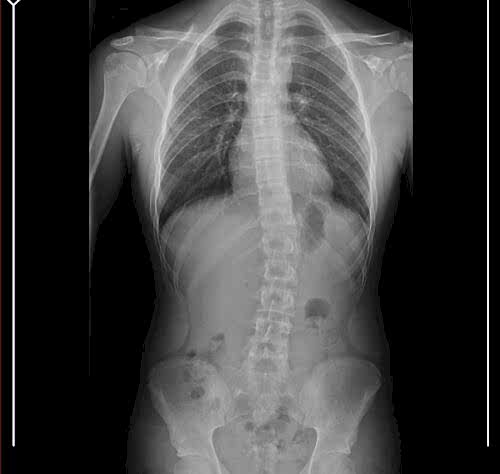

Skolyoz 3 boyutlu bir deformitedir. Tedavisinde ne kadar erken yaşta tespit edilirse düzeltme şansımız o…

Ankara Skolyoz ve Schroth Skolyoz Metod Tedavisi Skolyoz ve Schroth Skolyoz Metodu: Omurga eğriliklerinin 10°…

Ankara Schroth Skolyoz Tedavisi Düzgün Postür ve Daha Fazla Güvenliğin Anahtarı Skolyoz, bel ve…